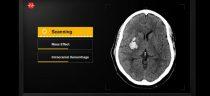

Компания Nines объявила о том, что ее система NinesAI на базе технологии искусственного интеллекта сертифицирована американскими регулирующими органами и доступна… далее

В условиях пандемии сочетание быстрой оценки результатов компьютерной томографии с клиническими результатами могло бы облегчить раннюю диагностику пневмонии COVID-19, позволяя, таким… далее